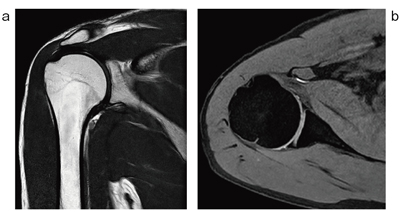

図6 Torso Coilによる肩関節の撮像例

Torso Coil(ds Torso Coil)で撮像した1.5Tの肩関節の画像例。左はプロトン密度強調画像,右は水選択励起による脂肪抑制画像である。Smart SelectによりFOVや断面に合わせて,エレメントの組み合わせが自動的に選択され,ベストな状態で撮像される。